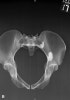

4. Judet Views (obturator oblique and iliac oblique)

Demonstrates: acetabulum

Helpful for: Acetabular fx

Position: Supine on cassette, roll the patient 45 degrees in relation to the x-ray beam. Consider premedication for pain. May be obtained digitally without rolling the patient (Patel NH, J Orthop Trauma 1998;12:59)°

Beam directed perpendicular to cassette.

위로 올라온 측면에서는 Acetabulum의 후면과 Obturator foramen

아래에 놓인 측면에서는 Acetabulum의 전면과 Iliac wing을 잘 관찰